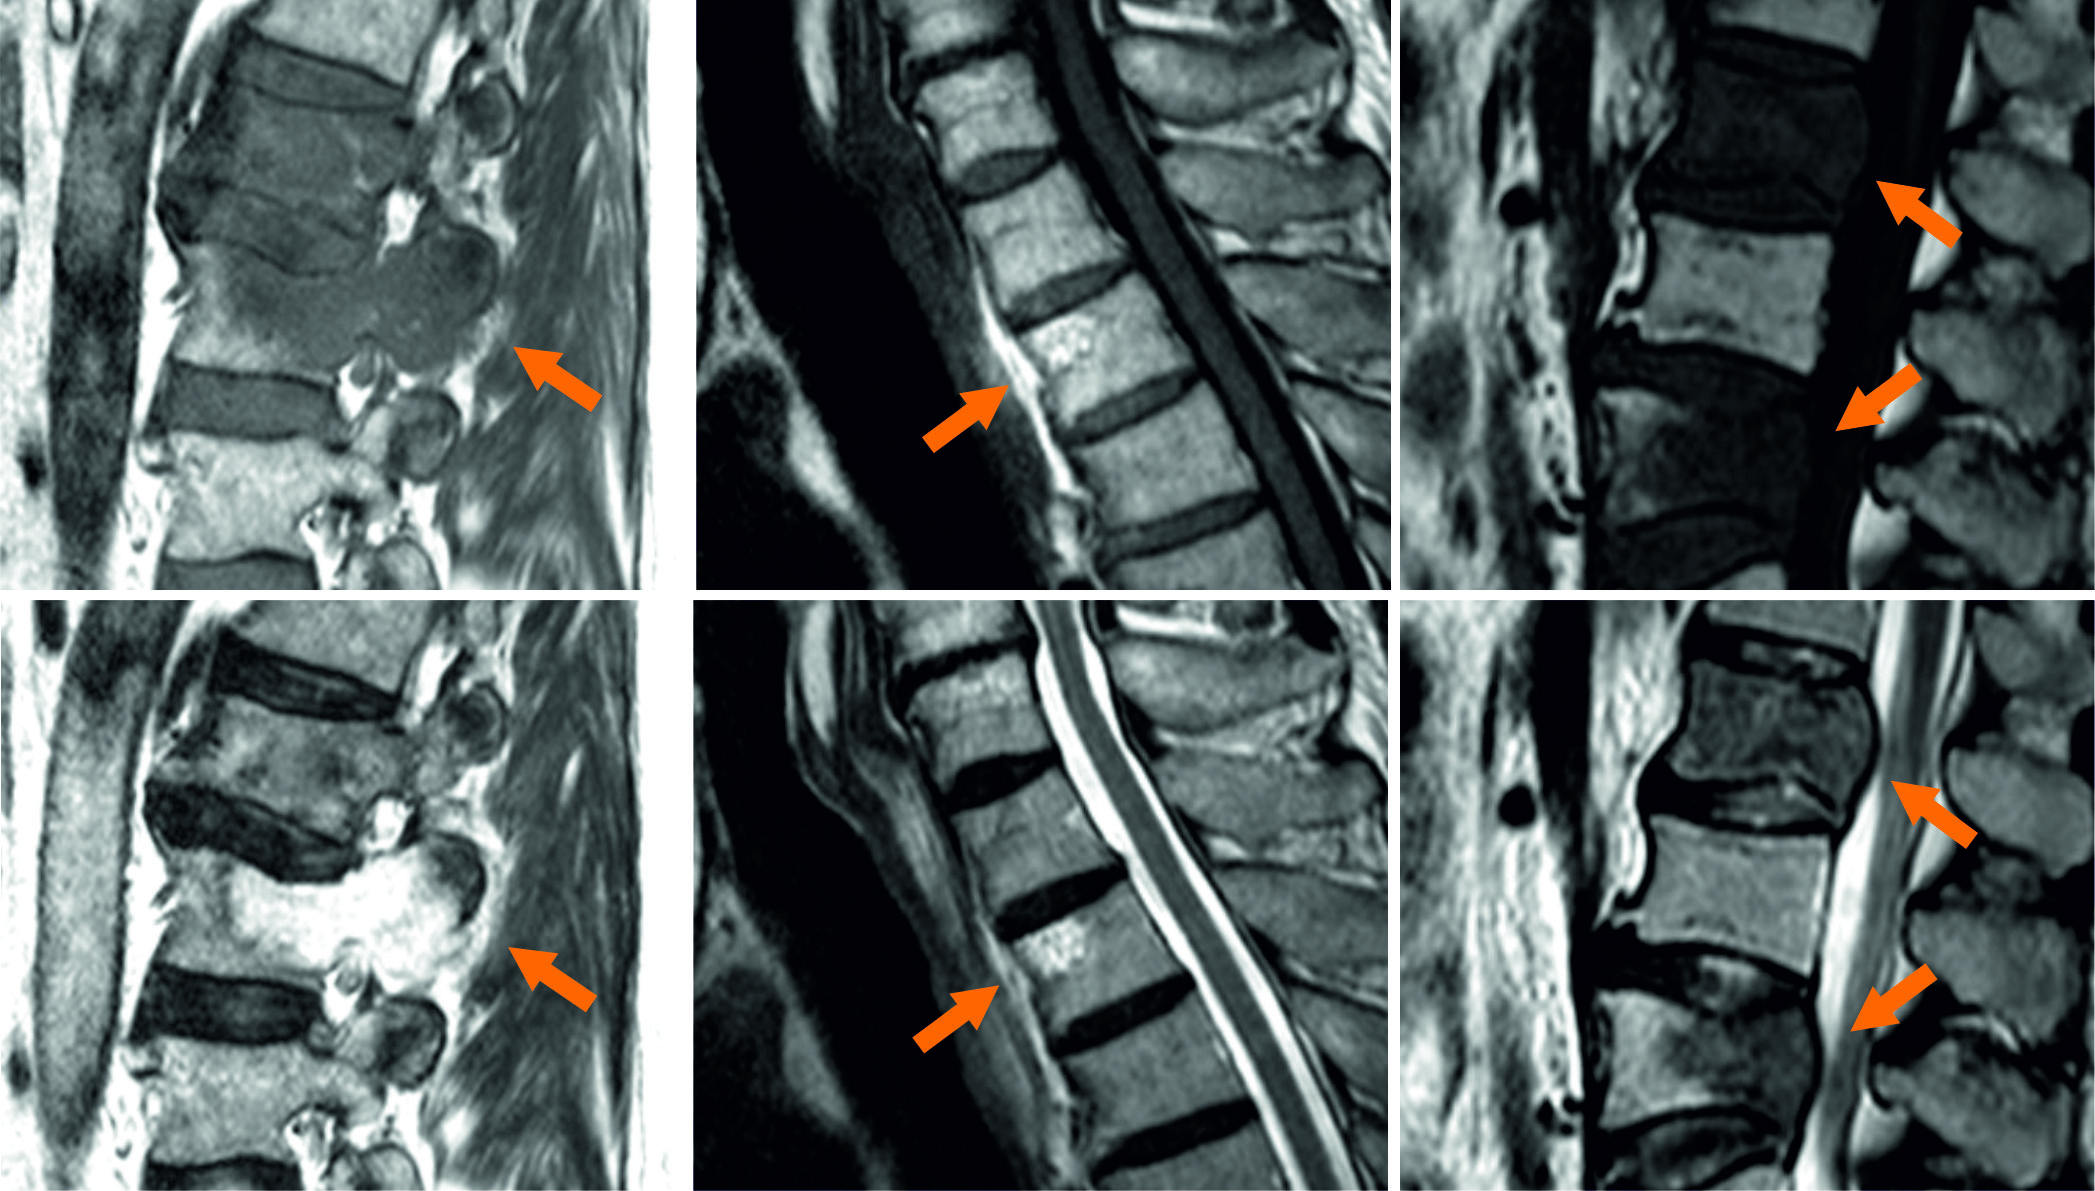

Due to the improvement of medical treatment and diagnostic procedures, life expectancy has increased steadily over the last decades. However, this lifetime gain promotes also age-related diseases like cardiovascular diseases, as well as cancer and cancer induced malicious metastases. The survival time of most malicious carcinomata has increased with improved diagnosis and treatment, hence, the probability to develop metastases raises. Beside liver and lung, bone metastases are the third most likely and thereof up to two thirds are located in the spine harrington1986metastatic ; wong1990spinal . Spinal metastases can tremendously affect the quality of life by evoking vigorous pain by fractures, bruises, spinal cord and nerve root compressions or neurologic deficits klimo2004surgical . Diagnosis and therapy planning can be done with multiple radiological imaging techniques, e.g. planar X-ray radiography, computed tomography (CT), single photon emission computed tomography (SPECT) or magnetic resonance imaging (MRI). The latter overcomes problems with radiation exposure of the aforementioned imaging techniques and has enhanced soft tissue contrast, which promotes early lesion detection and advanced diagnostic performance in terms of osseous lesions. Futhermore, spatial relationships of the metastazised vertebrae and surrounding tissues like the spinal cord or inter-vertebral discs are better visualized in MR than in CT or SPECT imaging. Dependending on their origin, there are two common types of bone metastases: lytic lesions, which lead to increased osseous tissue disruption due to further osteoclastic activity and sclerotic lesions, leading to increased osteoblastic activity and therefore, bone tissue production. The specific type tremendously affects the appearance of the metastases in the respective MR imaging sequences, ranging from hypo- to hyperintense image signals compared to non-pathologic vertebral bone structures (see Fig. 1), making this a highly challenging and ambitious task.